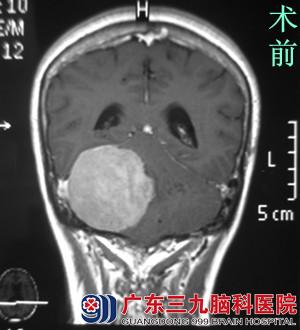

刚放暑假,易老师就被儿女催着去检查,结果当地医院行头颅CT检查后,提示右侧桥小脑角后部占位,易老师想着健康体检还真是不能忽视。为进一步明确病情,易老师来到广东三九脑科医院行头颅MR检查,提示:右侧小脑天幕示一较大的团块状占位性病变,大小约6.37*4.37*5.65cm,相邻脑组织明显受推压。完善相关检查后,由综合神经外科(神经外五科)鲁明主任主刀,在全麻下行右侧后颅窝巨大脑膜瘤切除术,术中显微镜下见灰白色肿瘤组织,质中,予超声刀分块切除,肿瘤侵犯横窦,在显微镜下全切肿瘤,手术顺利结束。术后易老师很快清醒,无任何的功能障碍,经过专科治疗护理,康复出院。术后病理结果:过渡型脑膜瘤(WHO I级)。